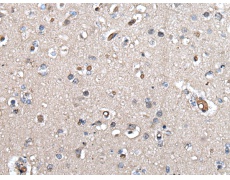

ELISA, IHC |

IHC positive control: |

Human brain |

IHC Recommend dilution: |

30-150 |